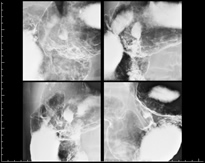

胃透視検査

この検査では胃がん・胃潰瘍・ポリープ・胃炎などの有無を検査します。

また同時に食道・十二指腸も検査します。

コップ一杯ほどのバリウムを飲んで行う胃の検査です。

バリウム以外に発泡剤と言う粉の薬も飲んでいただきます。ちょうど、ビールや炭酸飲料を飲んだ後のように、お腹が空気で膨らんでゲップが出そうになりますが、頑張って出さないようにしましょう。 この空気とバリウムで胃の中を満たし、細かい胃の粘膜を描出することができます。

上部食道・下部食道造影

上部食道・下部食道造影 胃バリウム正面像

胃バリウム正面像 体位を変えた胃バリウム像 凹状になった胃粘膜にバリウムが貯まっているのが分かります。

体位を変えた胃バリウム像 凹状になった胃粘膜にバリウムが貯まっているのが分かります。

子宮卵管造影検査

子宮卵管造影検査画像 子宮口より造影剤を注入してX線撮影をし、子宮の位置、形態、卵管の通過性や走行、腹腔内癒着の有無、卵巣の腫大などを調べる検査です。